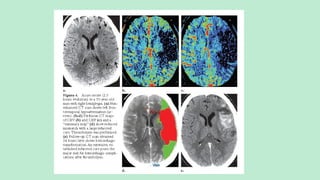

 CT perfusion maps

of cerebral blood volume

(a) and cerebral blood flow (b)

show, in the left hemisphere,

a region of decreased blood

volume (white oval) that corresponds

to the ischemic core

and a larger region of decreased

blood flow (black oval

in b) that includes the ischemic

core and a peripheral

region of salvageable tissue.

The difference between the

two maps (black oval white

oval) is the penumbra.

Ischemic core Region of dec. blood

Penumbra

Well perfused area